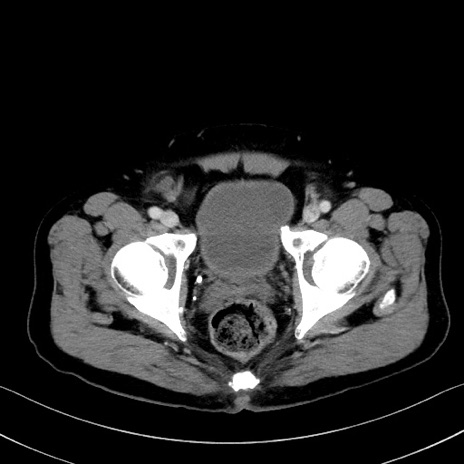

症例35(横断像)

【症例】70歳代 男性

【主訴】腹部膨満、嘔吐

【現病歴】昨日より腹部膨満感出現。本日増悪し、仙痛出現。嘔吐あり、受診。

【既往歴】糖尿病、胆摘後

【身体所見】BP 149/80mmHg、HR 74/min、BT 35.9℃、腹部:膨満、軟、圧痛なし。腸雑音減弱あり。上腹部正中切開瘢痕あり。

【データ】WBC 13500、CRP 1.72